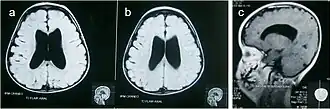

47,XXY/48,XXXY/49,XXXXY uwidaczniające niekomunikujące wodogłowie (A, B) i nieco hipoplastyczne ciało modzelowate (C)[20].W przeciwieństwie do chorych z kariotypem 48,XXYY i 48,XXXY, pacjenci 49,XXXXY są niscy; mają nasilone cechy dysmorficzne (hiperteloryzm, płaską nasadę nosa, mongoidalne ustawienie szpar powiekowych), mogą urodzić się z rozszczepem podniebienia i języczka, nierzadkie są wady wrodzone serca (najczęściej przetrwały przewód Botalla), synostoza promieniowo-łokciowa, stopa wydrążona (pes cavus), kolana koślawe (genu valgum), hipotonia i wiotkość w stawach. Również występują zaburzenia psychiczne. Fenotyp jest na tyle odrębny od fenotypu klasycznego zespołu Klinefeltera, że na określenie tej rzadkiej aneuploidii wprowadzono termin zespołu Fraccaro[20][21][22].

XXY, XXXY i XXXXY (odpowiednio, A B i C)[20].Rozpoznanie zespołu Klinefeltera można postawić jedynie na podstawie kariotypu. Prawidłowy kariotyp zmusza do dalszej diagnostyki – istnieje możliwość mozaicyzmu komórek somatycznych (np. 46,XY/47,XXY) albo zespołu mężczyzny XX. Inne jednostki chorobowe jakie należy uwzględnić w różnicowaniu to związane z nadmiernym wzrostem zespół łamliwego chromosomu X i zespół Marfana oraz zespół Kallmanna.